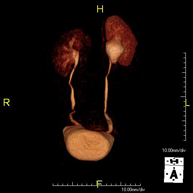

Prueba diagnóstica no invasiva que consiste en la obtención de imágenes de alta definición anatómica del hígado mediante el empleo de un campo electromagnético y ondas de radio (con un emisor y un receptor). No utiliza radiación ionizante. Se realiza para estudiar cualquier lesión localizada en el hígado, y también para valorar enfermedades inflamatorias y de depósito. Normalmente se requiere el uso de contraste paramagnético (Gadolinio) para caracterizar las lesiones. Es necesario realizar la prueba en ayunas (6 horas). - RM Riñones

Prueba diagnóstica no invasiva que consiste en la obtención de imágenes de alta definición anatómica de ambos riñones mediante el empleo de un campo electromagnético y ondas de radio (con un emisor y un receptor). No utiliza radiación ionizante. Se realiza para estudiar cualquier lesión localizada en ambos riñones. Normalmente se requiere el uso de contraste paramagnético (Gadolinio) para caracterizar las lesiones. - RM Glándulas Suprarrenales